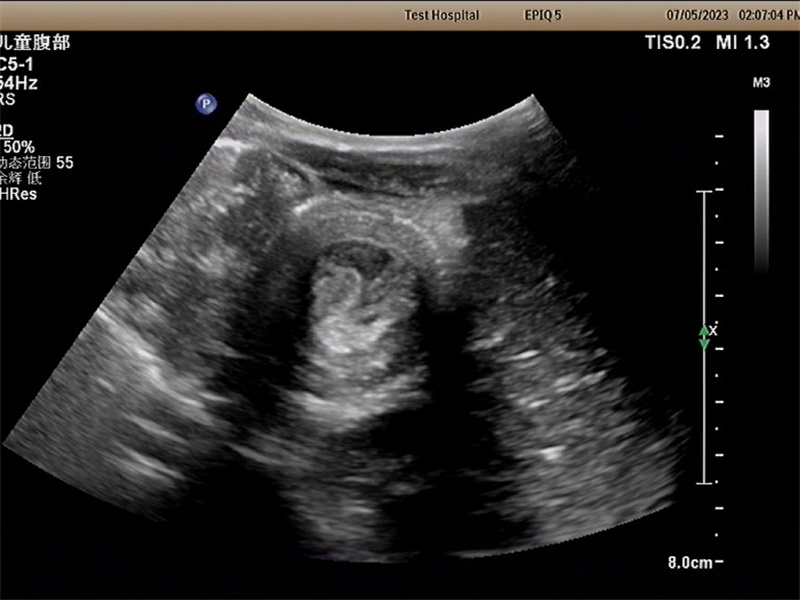

徐州市儿童医院科普:小儿腹痛之“肠套叠” 留心症状与家长须知